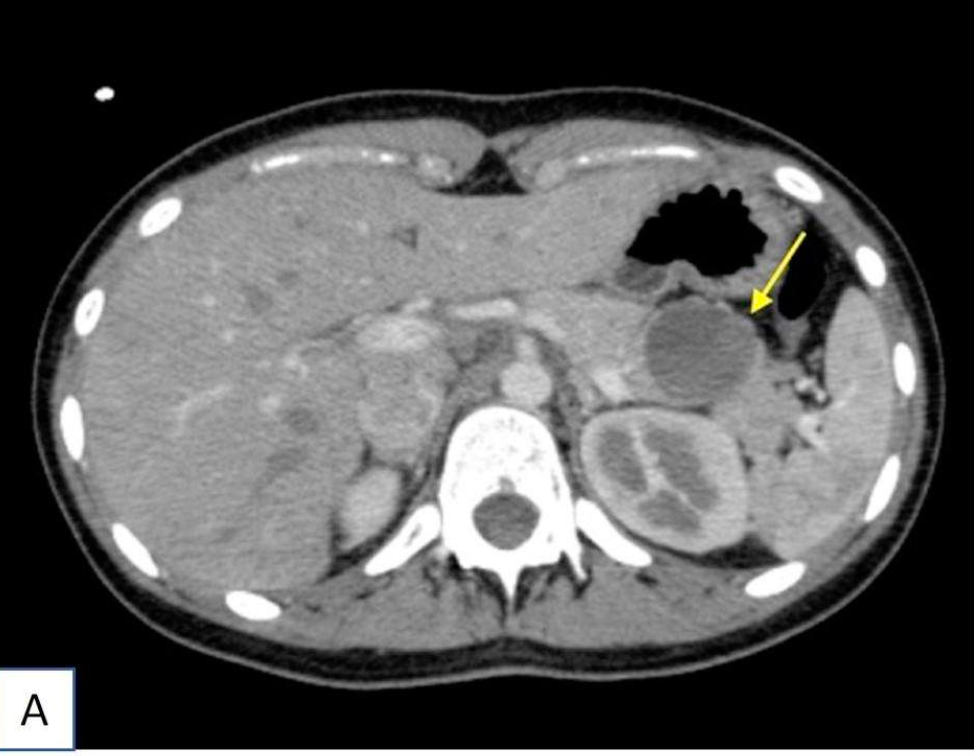

31세 여자가 등과 옆구리의 간헐적 통증으로 병원에 왔다. 복부 전산화 단층촬영(사진 A)에서 췌장 미부에 비교적 경계가 좋은 장경 3 cm 크기의 낭성 종양이 발견되어 절제술을 시행하였다. 사진(사진 B)은 이 종양의 조직학적 소견 및 β-catenin에 대한 면역조직화학 염색 결과이며, β-catenin 유전자 (CTNNB1)의 돌연변이가 관찰되었다. 진단은?

• 주로 급성 췌장염의 부작용으로, 환자의 10-20%에서 1-4주 뒤에 발생한다. Epithelial lining 대신 fibrosis과 granulation tissue로 둘러싸여 있는 것이 조직학적 특징이다. 복부 CT에서는 얇은 벽으로 둘러싸인 저음영의 커다란 낭종이 관찰된다. 심한 통증이 동반되거나 파열, 농양, 감염, 출혈 등의 합병증이 생길 시 배액술을 시행하고 그렇지 않은 경우는 대증치료를 하며 경과 관찰한다.